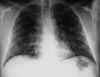

Chest radiographs are ordered.

Chest radiographic abnormalities are seen in up to half of all symptomatic patients. Typically, infiltrates are associated with ipsilateral hilar adenopathy. Peripneumonic pleural effusion may occur.

Diffuse pneumonia may also result from hematogenous spread. This is a rapidly progressive condition seen most commonly in immunocompromised patients; it may cause respiratory failure. Chest radiographs typically show a diffuse reticulonodular pattern throughout both lung fields.